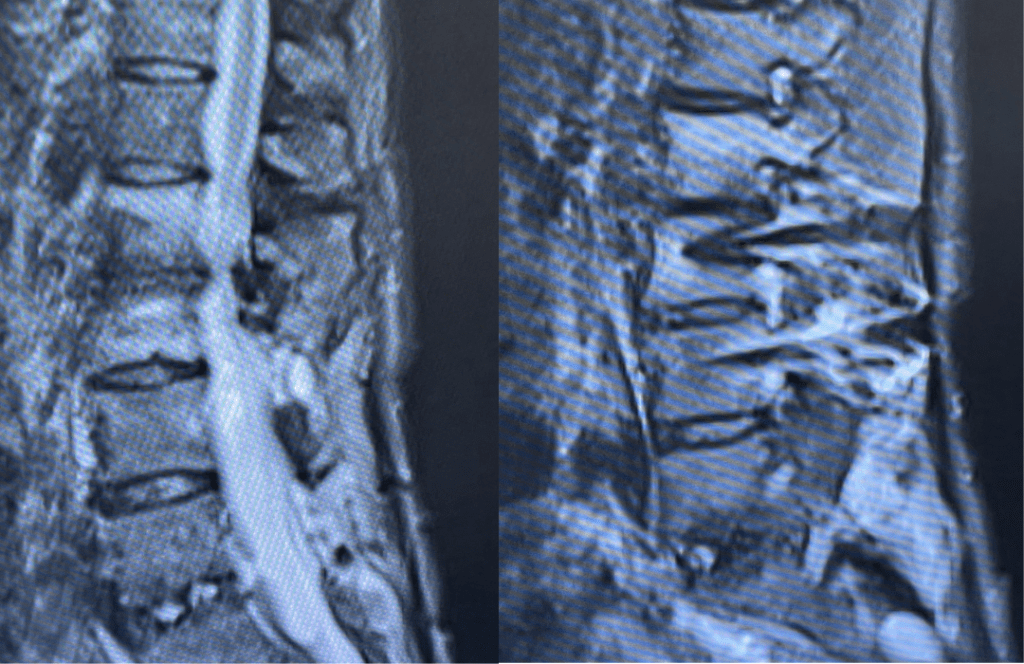

Figures 1a and 1b. Sagittal T2 MRIs of the lumbar spine demonstrating L2-3 stenosis after L3-4 instrumented fusion.

This 62-year-old female presents with chronic intractable low back pain with radiation down the front of her thighs. The patient had had two prior fusion surgeries: She initially had an L4-S1 fusion twelve years prior and a subsequent revision extension of her fusion at L3-4 that she had three years prior. She had a long-term history of smoking. She had mild hip flexor weakness, right greater than left. Imaging studies revealed next segment degeneration and stenosis at L2-3 (Figs. 1a and 1b and 2).